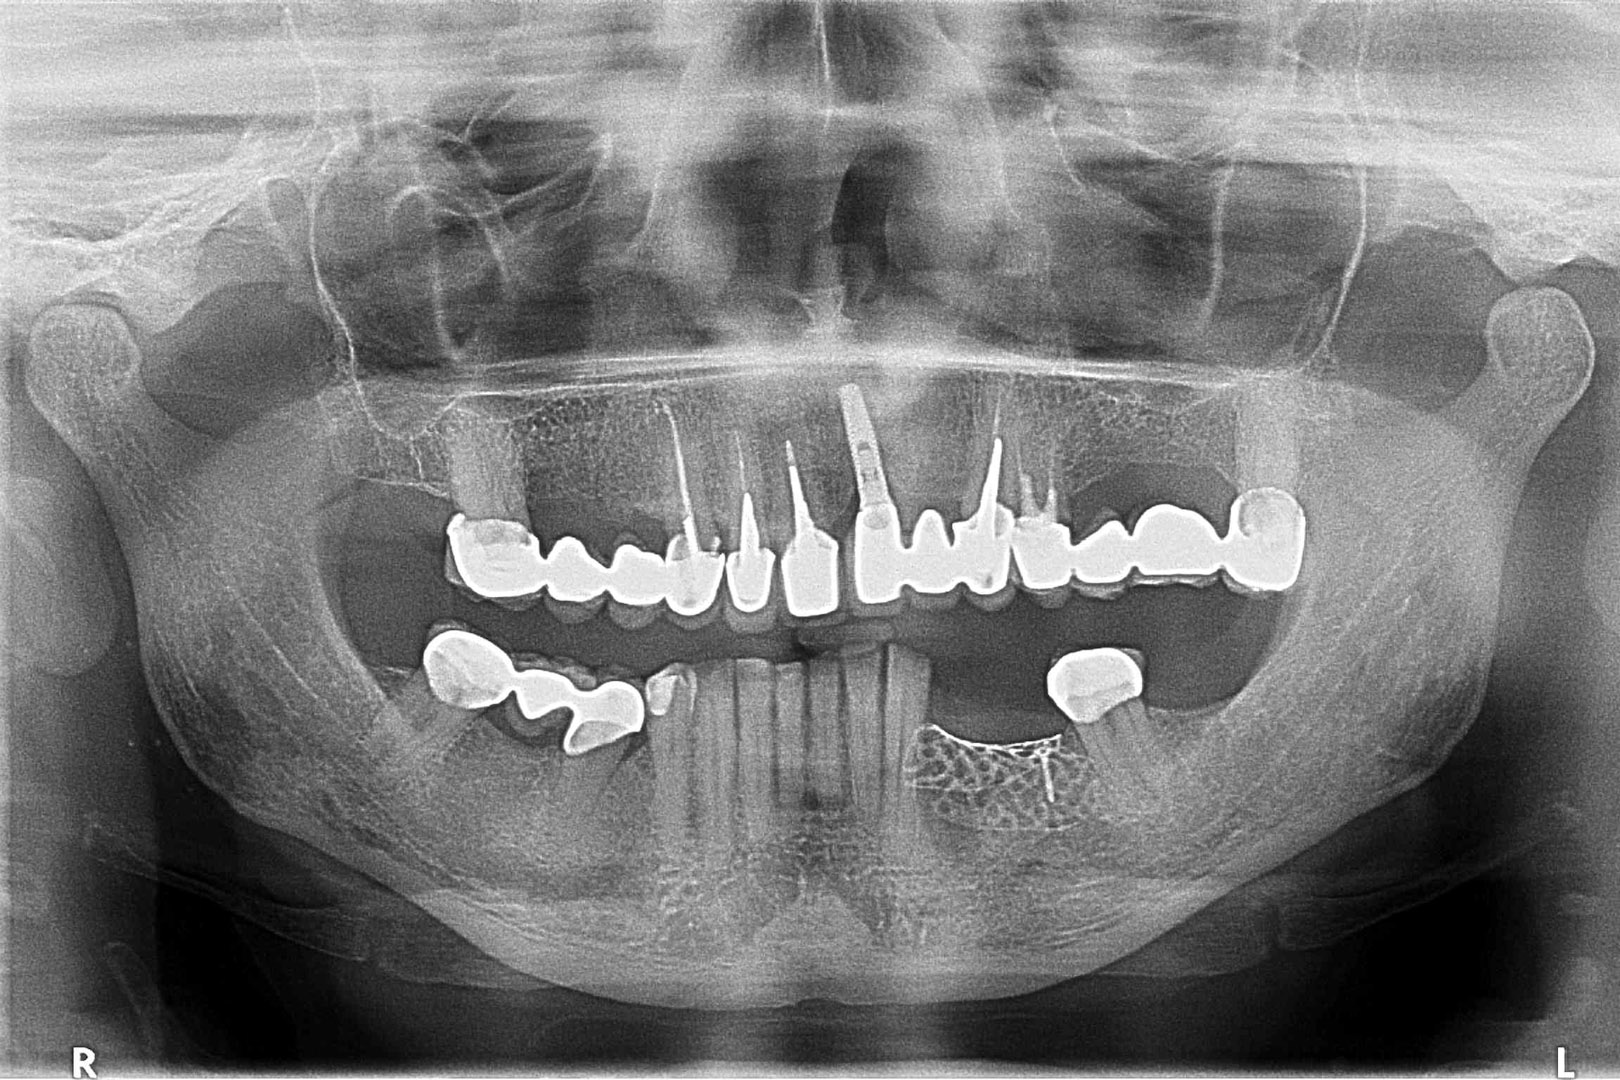

Przed podjęciem leczenia należy określić stopień zaniku kości szczęk oraz żuchwy. W tym celu przeprowadza się badanie kliniczne oraz odpowiednią diagnostykę obrazową pacjenta. Uwzględnia ona zdjęcie panoramiczne OPG jako podstawę dwuwymiarowego obrazowania podłoża kostnego oraz możliwe jest badanie tomograficzne CT lub bardziej precyzyjna tomografia stożkowa CBCT. Opcjonalnie wykorzystywana diagnostycznie tomografia pozwala na bardziej wnikliwą ocenę stopnia zaniku kości w trójwymiarowym, przestrzennym obrazie.